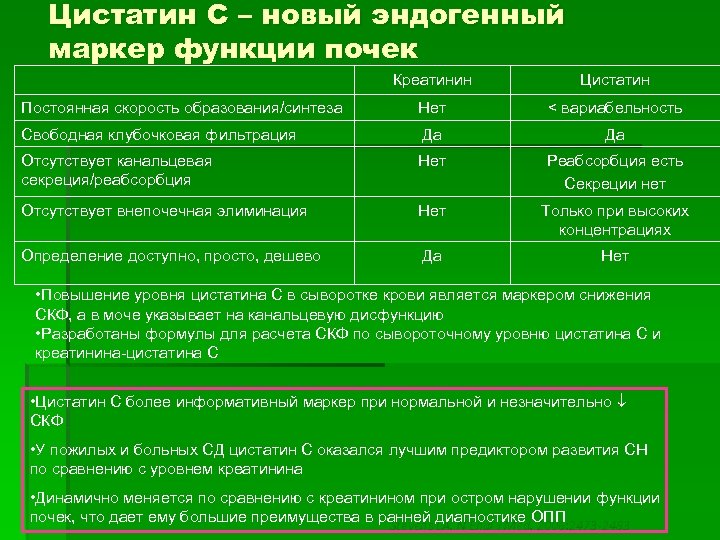

Цистатин С – новый эндогенный маркер функции почек Креатинин Цистатин Постоянная скорость образования/синтеза Нет < вариабельность Свободная клубочковая фильтрация Да Да Отсутствует канальцевая секреция/реабсорбция Нет Реабсорбция есть Секреции нет Отсутствует внепочечная элиминация Нет Только при высоких концентрациях Определение доступно, просто, дешево Да Нет • Повышение уровня цистатина С в сыворотке крови является маркером снижения СКФ, а в моче указывает на канальцевую дисфункцию • Разработаны формулы для расчета СКФ по сывороточному уровню цистатина С и креатинина-цистатина С • Цистатин С более информативный маркер при нормальной и незначительно СКФ • У пожилых и больных СД цистатин С оказался лучшим предиктором развития СН по сравнению с уровнем креатинина • Динамично меняется по сравнению с креатинином при остром нарушении функции почек, что дает ему большие преимущества в ранней диагностике ОПП Stevens LA. N Engl J Med. 2006: 2473 -2483